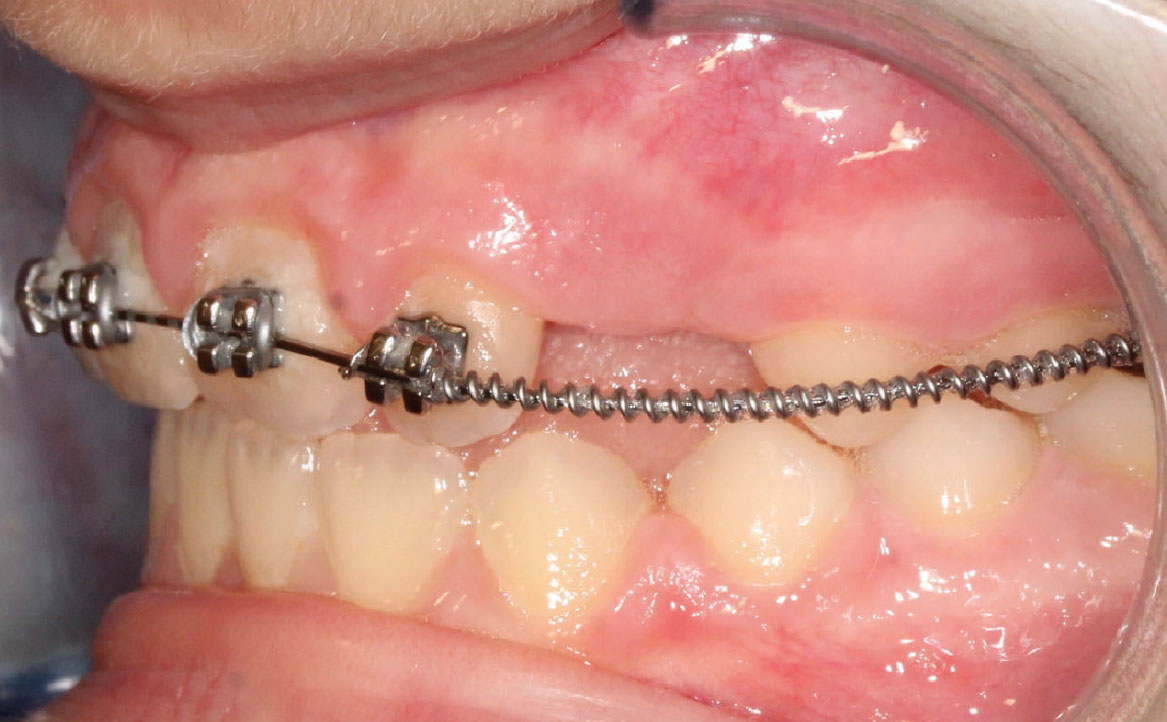

A 9 mesi dal montaggio dell’apparecchiatura overjet risulta positivo e gli elementi 13 e 23 sono in eruzione.

È ora assente lo shift anteriore (fig. 9).

Fig. 9A Dopo 9 mesi dall'inizio del trattamento ortodontico

Fig. 9B Dopo 9 mesi dall'inizio del trattamento ortodontico